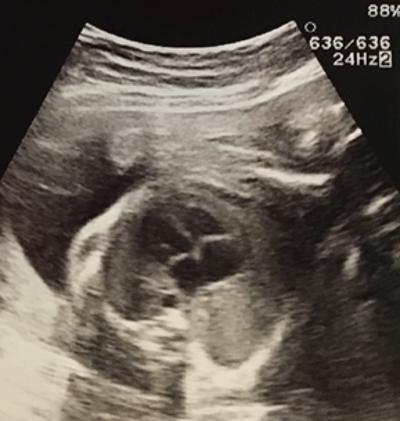

また、腹部の膨隆に対して腹部超音波をあてたところ、以下の所見が得られた。

■腹部超音波